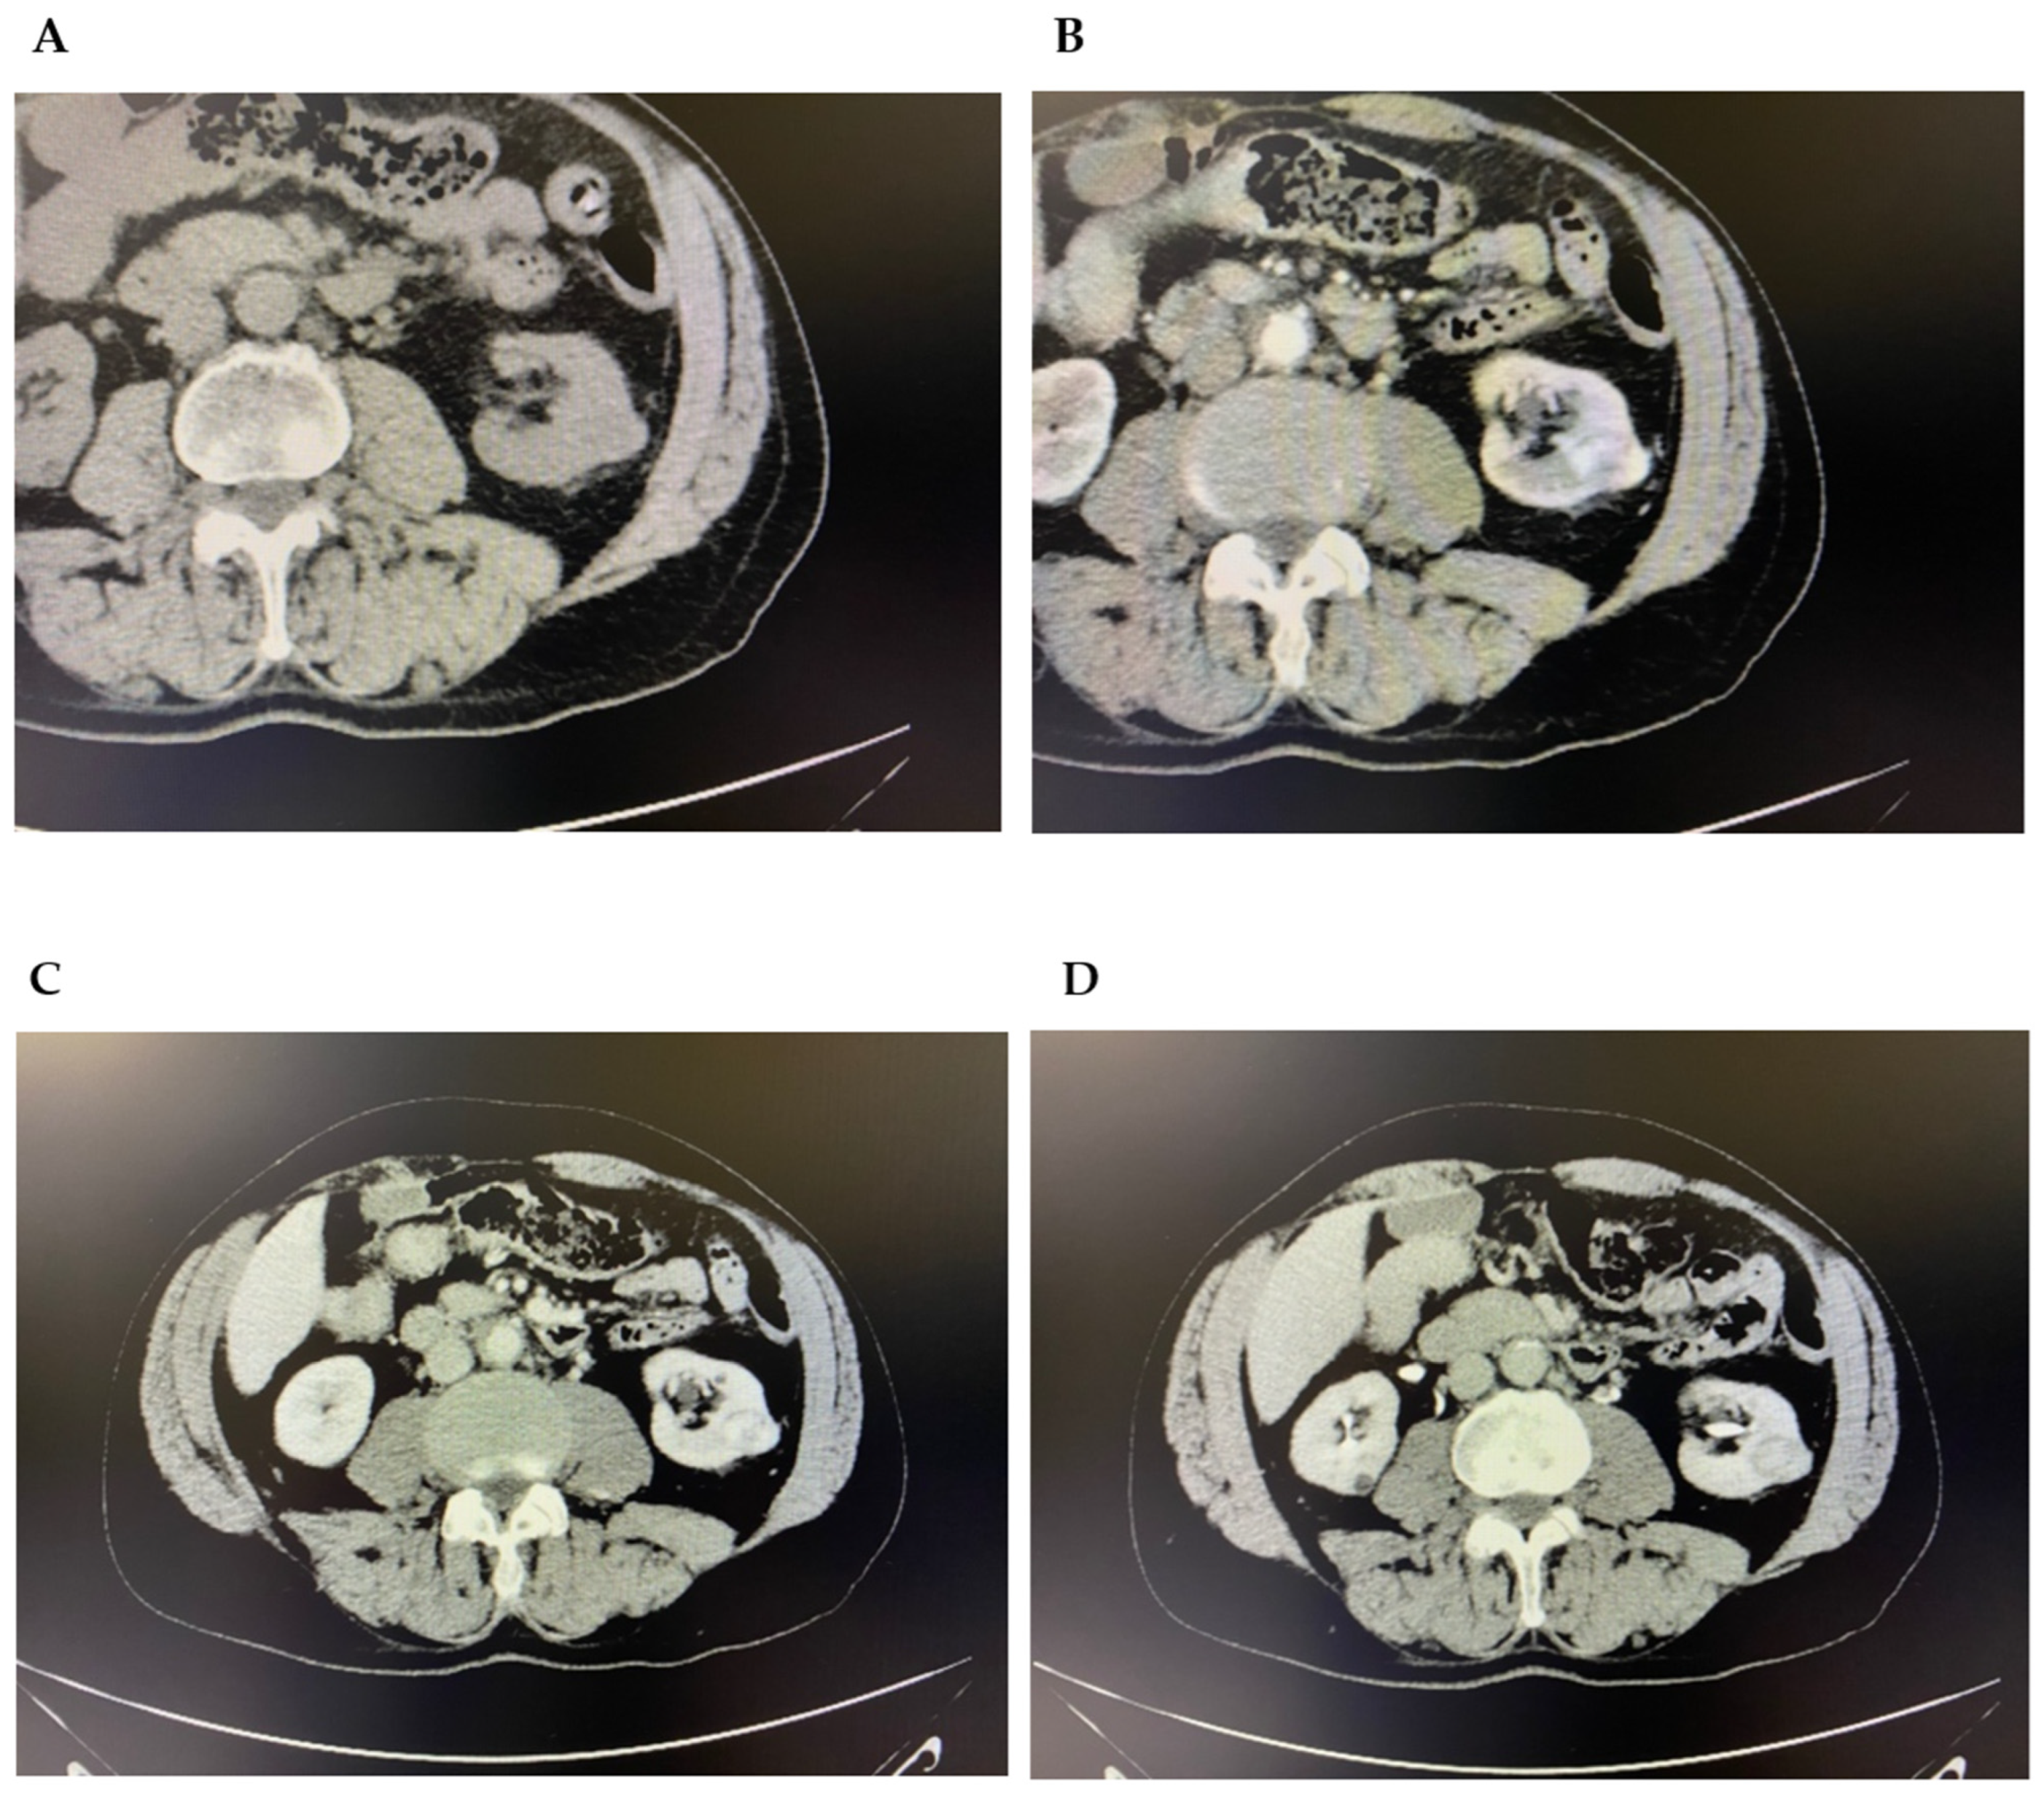

2. Case Presentation

5.4. Magnetic Resonance Imaging